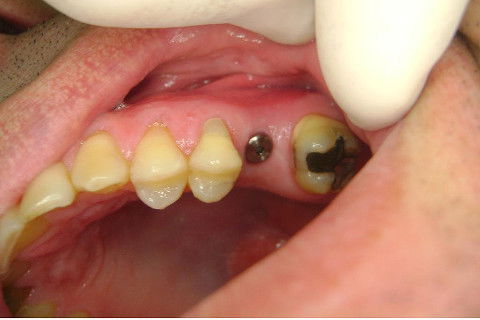

Instalação de um implante em região do 26. Utilizamos um implante cone morse Alvim Neodent 4.3 X 11,5. Foi uma cirurgia muito rápída e minimamente traumática, sem retalho e sutura.

Fotos do caso